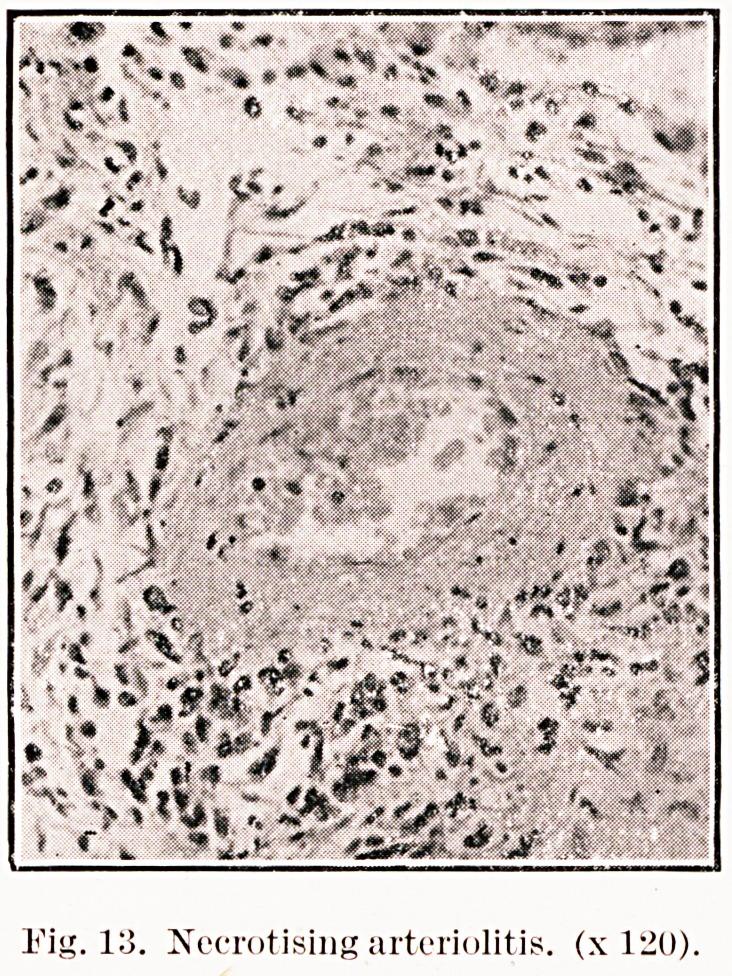

The rheumatic lung; report of two cases.

Glasgow Med J. 1947 May;28(5):127-33.